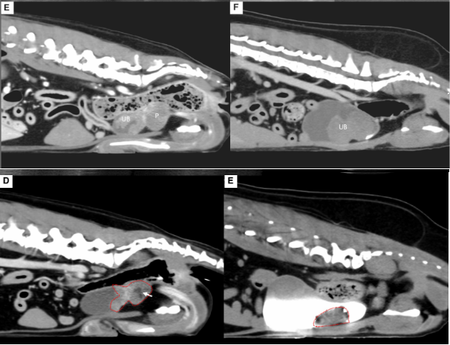

첫 번째 논문은 거대 방광 종양으로 지속적인 혈뇨와 빈혈을 보인 개 2마리에서 종양 색전술을 적용한 사례로 'Journal of Small Animal Practice(SCI)'에 게재됐다.

전통적으로 비뇨기 종양 색전술은 합병증 위험으로 전립선 종양에만 국한됐지만 본 증례는 종양으로 공급되는 혈관만을 초선택(superselective) 했고, 시간이 지나 재개통이 되는 색전 물질(gelatin sponge particle)을 이용해 효과를 극대화 하면서도 심각한 합병증이 발생하지 않도록 하였다.

시술 직후 혈뇨는 즉시 개선됐으며, 배뇨곤란 증상도 완화됐다. 또한 종양 크기는 50% 이상 감소했으며, 빈혈과 혈소판 감소증을 보였던 환자에서도 4주만에 혈액 수치가 정상화 되었다.

해마루 인터벤션센터는 현재까지 하부 비뇨기 종양 색전술을 200례 이상 시행했으며, 30여 마리를 장기 추적한 전향적 연구도 유명 SCI 저널 게재를 앞두고 있다.